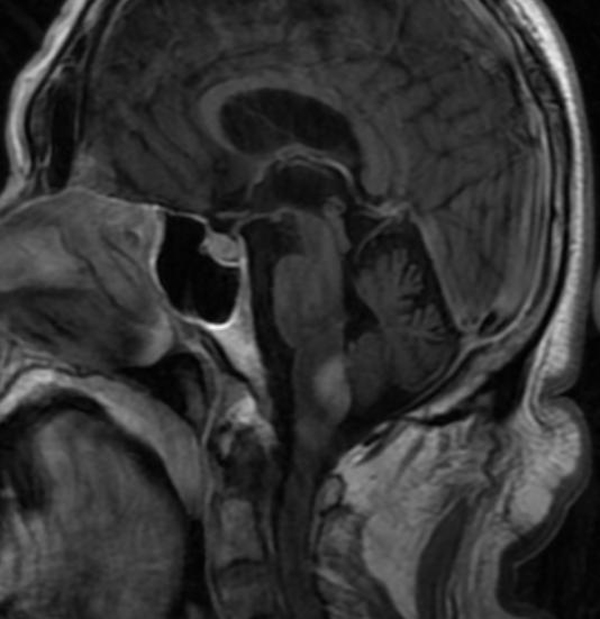

73岁的刘大爷因“言语不利、饮水呛咳及肢体无力”在当地医院以“脑梗塞”住院治疗10天,症状进行性加重,转入二一五医院进一步治疗,神经外科肖三潮教授、谢国强主任通过全院多学科会诊,经过充分评估患者病情后考虑,目前肿瘤占位效应明显,压迫延髓,导致患者呼吸功能紊乱,随时存在呼吸停止可能,唯有尽快手术切除肿瘤才能挽救患者生命,但延髓手术风险极大,术中患者随时存在呼吸心跳骤停可能,向患者家属充分告知手术必要性及危险性,征得家属同意后,12月27日,神经外科肖三潮教授、神经重症监护室谢国强主任、吴东飞主治医师在全麻下为患者行延髓占位切除术。

术中保留患者自主呼吸,严密检测生命体征变化,术中多次出现呼吸及心跳减慢,麻醉师予以兴奋呼吸等积极治疗,最终转危为安,历时6小时,手术顺利完成。术后患者神志清楚,术后三天脱机,右侧肢体功能正常,左侧肢体肌力同术前(3级),目前正在逐步康复中。